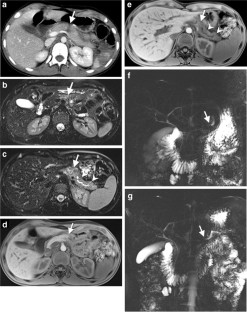

Of 3,265 patients presented as trauma team activations during the study period, only 28 (0.86%) children (19 boys, 9 girls; mean age: 7.14 years; age range: 1–15 years) had pancreatic injury. Of the available 27 CTs of the abdomen, 26 were performed on the day of trauma. Associated injuries were seen in 25/27 children, most frequently in the liver and lung, 16 (59.2%) each. There were 5 (19%) Grade I, 9 (33%) Grade II, 8 (30%) Grade III and 3 (11%) Grade IV. No patients had Grade V injury. No pancreatic parenchymal injury was identified in 2 (7%) patients with isolated fluid around the pancreas and mesentery. The pancreatic duct was visible in all 10 children (days: 0–330, median days: 41 post-trauma) who had MRI. Eight of these children, who had Grade III/IV injuries on CT and confirmed pancreatic duct injury on endoscopic retrograde cholangiopancreatography (ERCP) or surgery, showed either signal intensity difference in pancreatic parenchyma and/or caliber difference in the pancreatic duct proximal and distal to the injury site. Two patients died because of multiorgan injuries, 9 patients (mainly with Grade III and IV injuries) underwent surgery and/or ERCP, and 16 patients were managed conservatively. AAST grading of pancreatic injury on CT correlated with type of management (P=0.0001) with most of the Grade III and IV injuries treated with intervention and/or surgery while all of the Grade I and II injuries were treated conservatively.

Pancreatic injury is rare in children but often associated with other organ injuries most frequently involving the liver and lung. CT grading of injury correlates with management and guides intervention and/or surgery versus conservative treatment. MRI is useful for assessing pancreatic duct injury by demonstrating the pancreatic duct directly and/or secondary changes like signal intensity difference in pancreatic parenchyma and caliber difference in the pancreatic duct.

Fig. 3